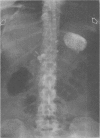

A case of hepatoma induced by thorium dioxide (Thorotrast) is reported. The literature concerning neoplasia associated with this agent is reviewed, with emphasis on the long latent period before the development of these tumours and the equally long latent period which preceded the recognition of their iatrogenic nature.

In particular, this report is intended to illustrate the diagnosis of such tumours on radiological and histological findings, provided that one is aware of their existence and familiar with the distribution and appearance of thorium dioxide deposits in the tissues. Such a diagnosis can be made without a history of thorium dioxide administration, which often may not be available.